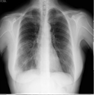

4.1. Data Processing

- GGOs.

- Odd paving pattern.

- Consolidation of the airspace.

- Thickening of bronchovascular bundles.

- Traction bronchiectasis.

- Reticular opacities.

- Vascular thickness.

- Additional widespread distribution along the bronchovascular bundles.

- Thickness in bronchial wall.